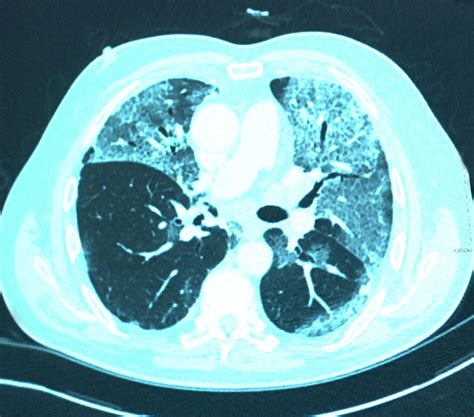

Receiving medical imaging results can often feel overwhelming, especially when terms like lung scarring on CT scan appear on your radiology report. Finding evidence of scarring—medically referred to as pulmonary fibrosis or interstitial lung abnormalities—can trigger anxiety, but it is important to remember that these findings are descriptive and require clinical context to be fully understood. A CT scan is a highly sensitive diagnostic tool that provides a detailed cross-sectional view of the lungs, allowing doctors to identify changes in the lung tissue that might not be visible on a standard chest X-ray. Understanding what this scarring means, why it happens, and what steps you should take next is the first step toward managing your respiratory health effectively.

When your doctor discusses lung scarring on CT scan, they are looking at specific patterns that tell a story about the lung’s history. Radiologists often use specific terminology to describe the appearance of these changes. Here is a simplified table of common radiological findings and their general implications:

Radiological Term What It Usually Implies

Reticulation A net-like pattern indicating mild thickening of the lung structure.

Honeycombing Clusters of cystic air spaces; often suggests advanced or established scarring.

Ground-Glass Opacities Hazy areas; these may indicate active inflammation that could be reversible, rather than permanent scar tissue.

Traction Bronchiectasis The pulling open of airways due to the contraction of surrounding scar tissue.

💡 Note: A radiological term does not equal a diagnosis. Your physician must correlate these imaging patterns with your medical history, blood work, and physical examinations before confirming any specific lung condition.